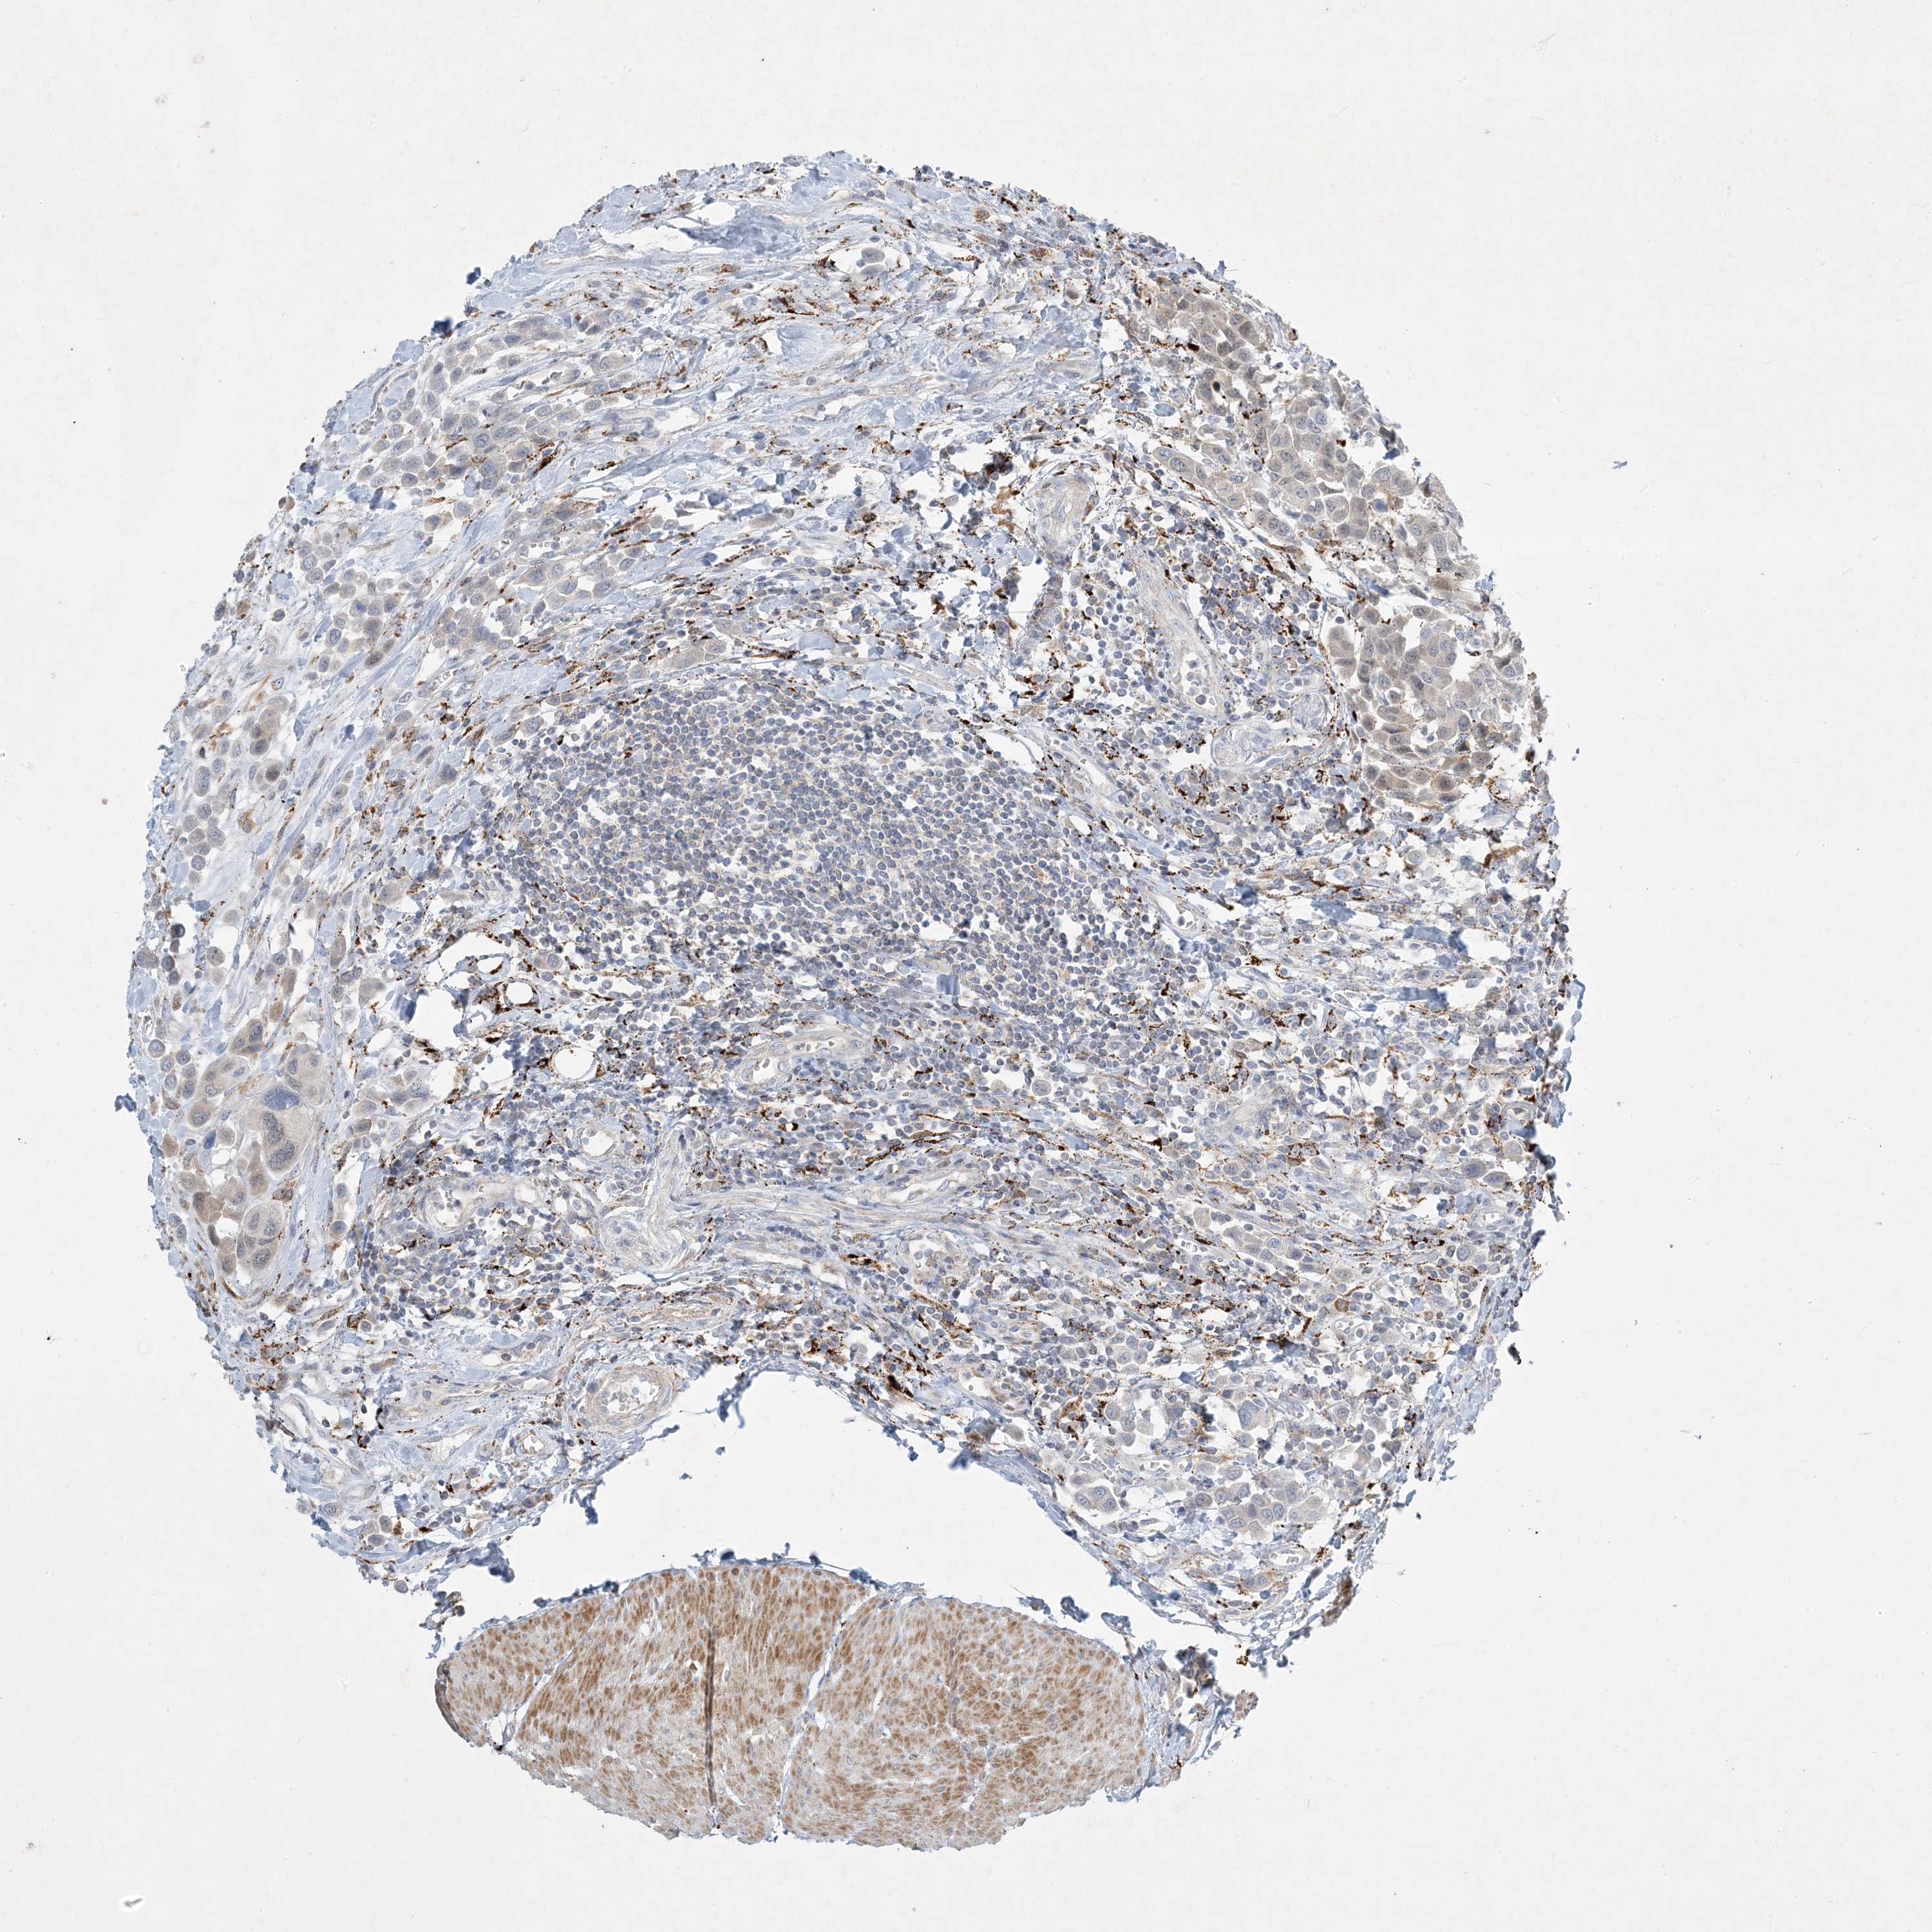

UROTHELIAL CANCER - Protein expressioni

A mouse-over function shows sample information and annotation data. Click on an image to view it in a full screen mode. Samples can be filtered based on level of antibody staining by selecting one or several of the following categories: high, medium, low and not detected. The assay and annotation is described here.

Antibody stainingi

Antibody staining in the annotated cell types in the current human tissue is reported as not detected, low, medium, or high, based on conventional immunohistochemistry profiling in selected tissues. This score is based on the combination of the staining intensity and fraction of stained cells.

Each image is clickable and will lead to virtual microscopy that enables deeper exploration of all samples and also displays staining intensity scores, fraction scores and subcellular localization as well as patient and tissue information for each sample.

Antibody HPA029143

Antibody CAB034164

Urothelial carcinoma, Low grade

Urothelial carcinoma, High grade